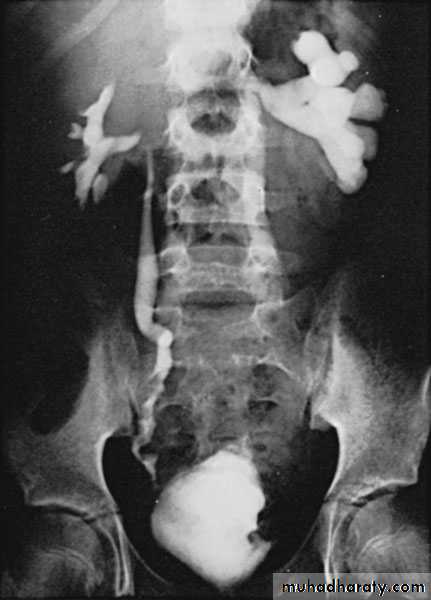

KUB: obscured psoas shadow, spine scoliosis,.

Drinage of perinephric abscess